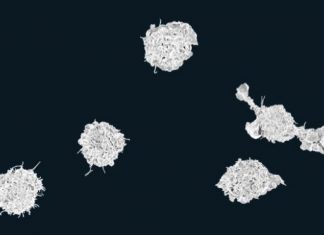

愈來愈多證據顯示,流感病毒可以附著於懸浮微粒上,所以只要感染者搭電梯後,下一位乘客就可能被感染;流感的感染力已超乎預期的嚴重,在台灣,一週內因類流感去急診的就診人次超過 12 萬人,美國這次也遇到 10 年以來最嚴重的流感。目前,美國的醫療系統持續和本世紀以來最嚴重的流感疫情抗戰,美國疾病管制局資料顯示,近 2 萬名病患因流感而住院治療。這一數字與 2014 年發生的嚴重流感疫情相當,但這次死亡人數不斷上升,令人擔憂;尤其流感季節尚未達高峰期,專家預期,整個疫情會比 2014 年更嚴峻,醫院會被擠爆。醫療數位工具  愈來愈普及不過,全美知名的波士頓兒童醫院創新研發部主管布朗斯坦,從來自數位化醫療包括遠端視訊醫療和連接雲端的診斷醫材公司的數據分析發現,線上虛擬(chatbots)或真人問診,在這次流感爆發期間,有效分流過去病患須到實體醫院或診所治療,協助解決現有醫療體系不足的窘態。從遠距視訊醫療公司的統計資料顯示,今年流感嚴重期,求助遠端醫療的人數暴增,美國知名遠距醫療服務公司 American Well 醫療部門的主管 Sylvia Romm 說,最近該公司線上流感問診大幅成長 3 倍之多。全美最大遠距視訊醫療平台公司...